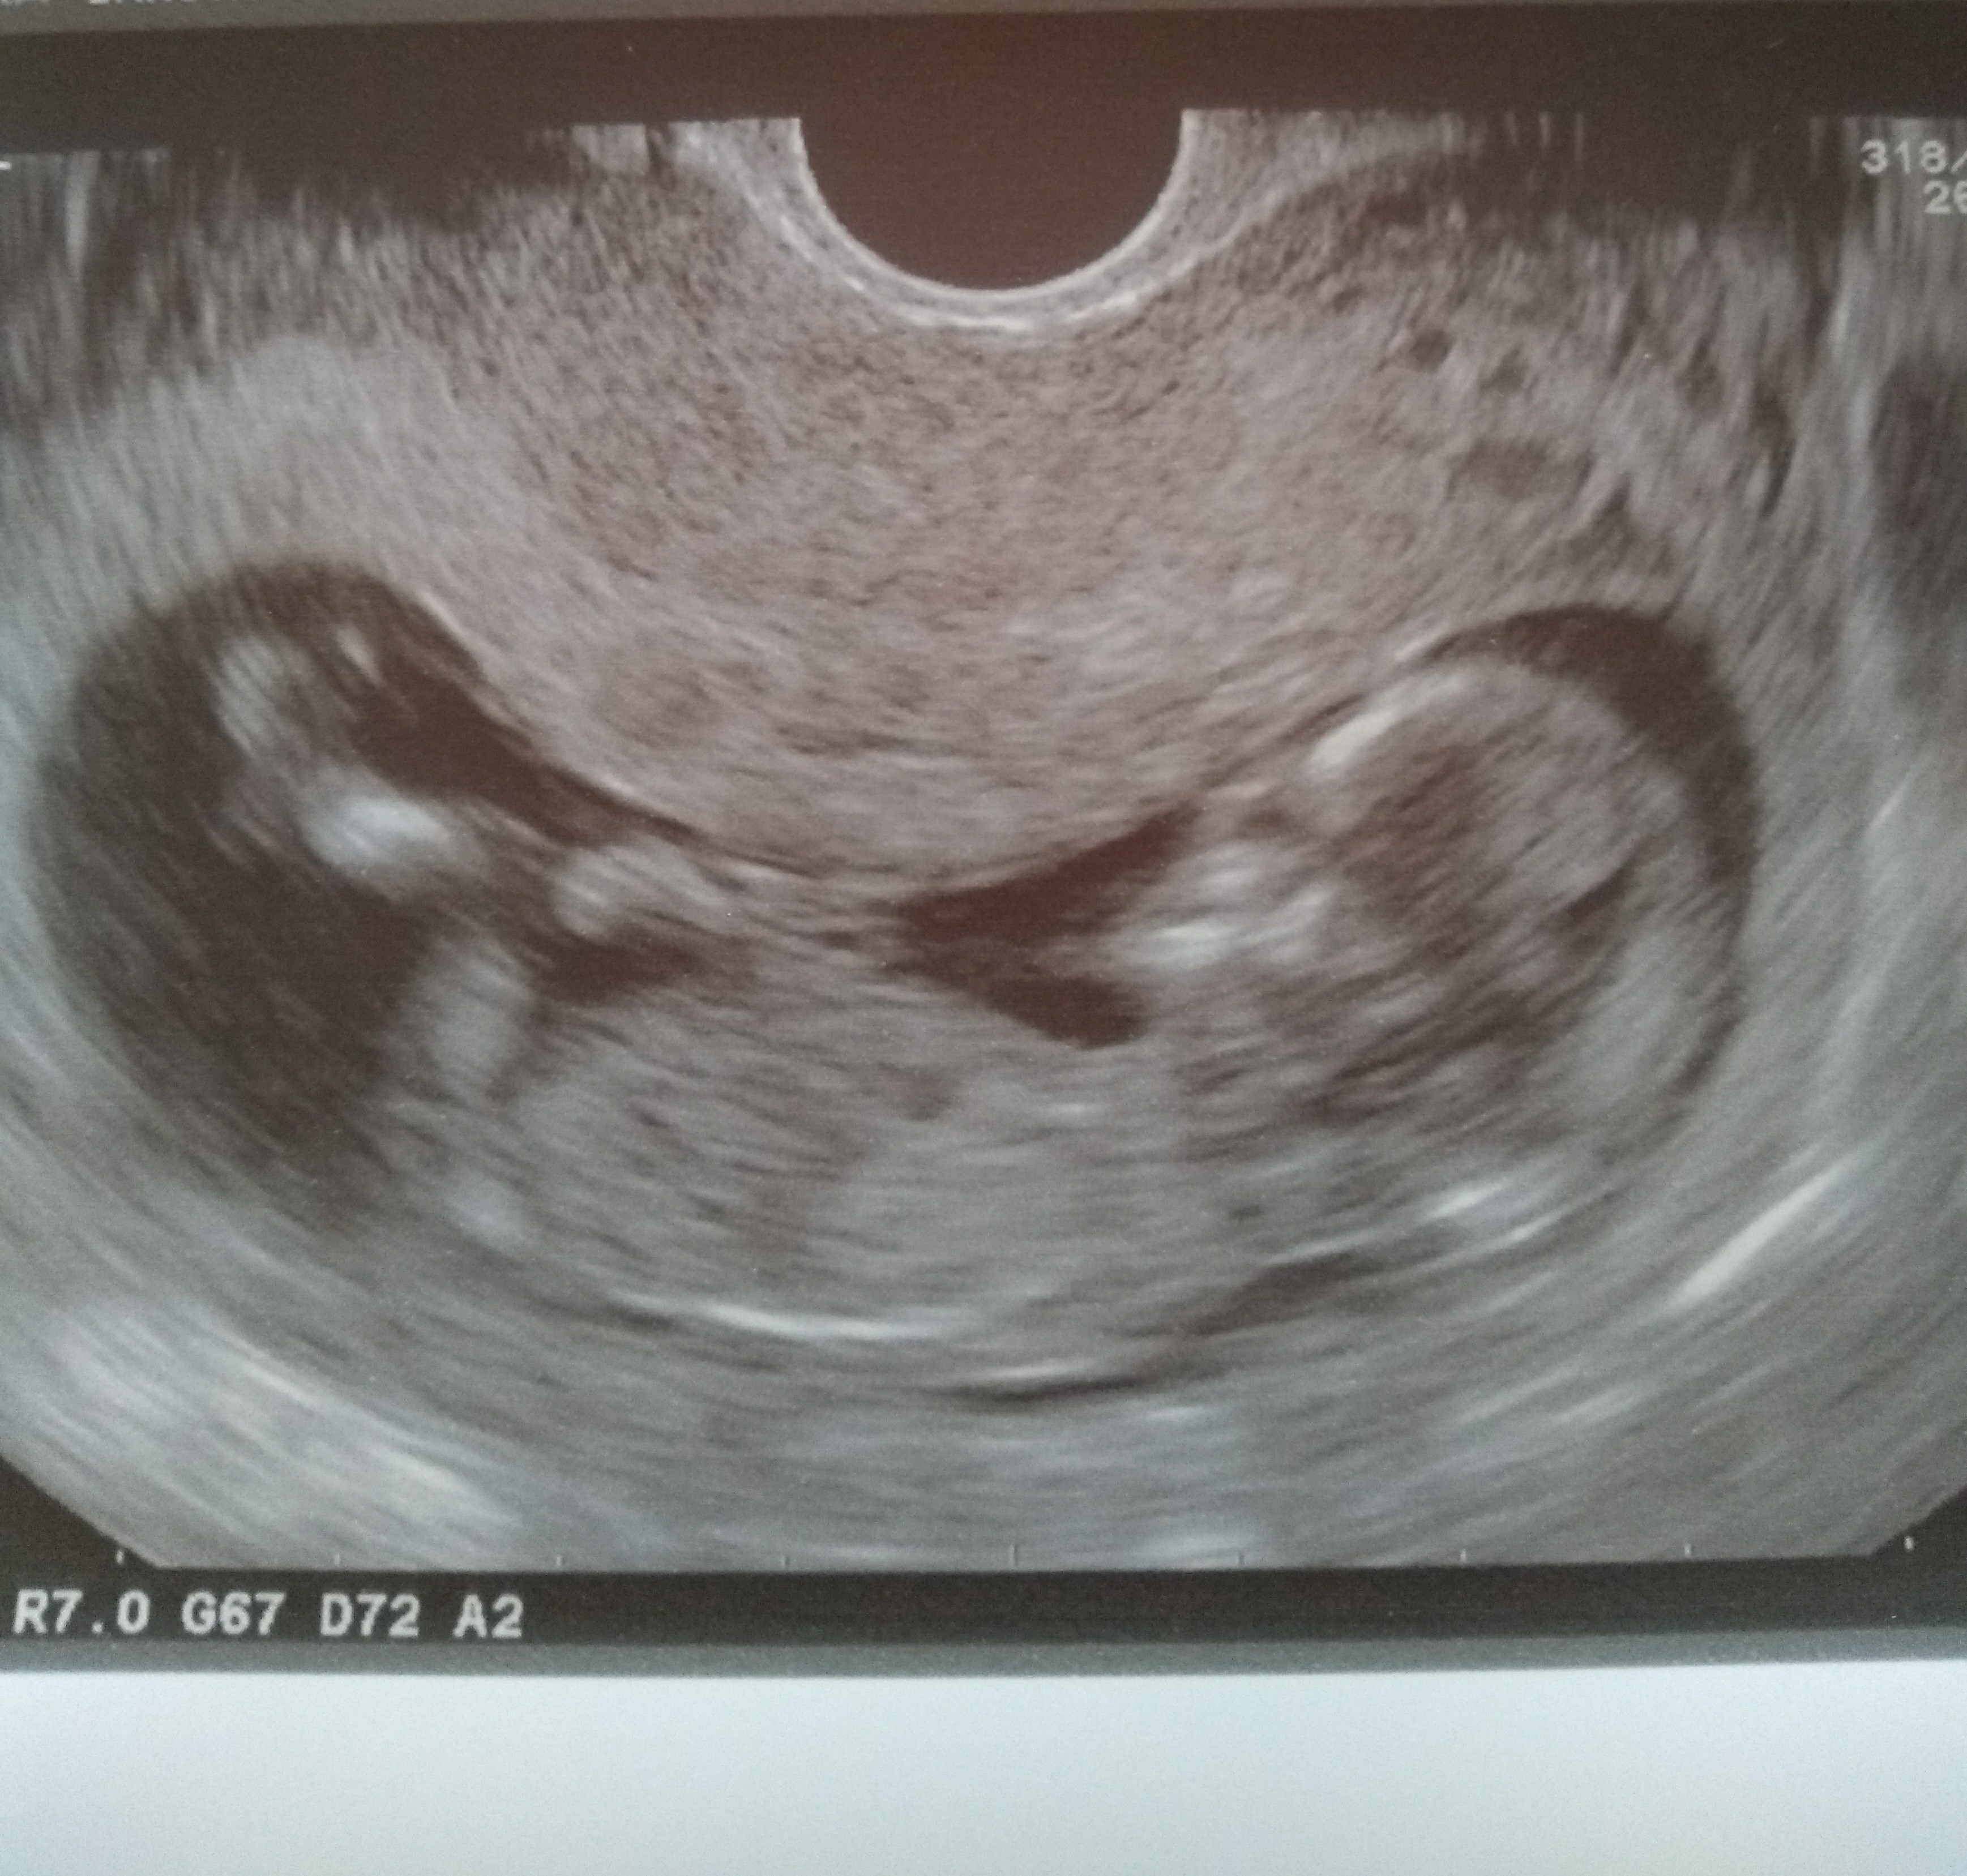

No ja już po :) wszystko jest ok, maleństwo ma 6,5 cm. Przezierność karczku to 1,5. Wychodzi że to 12t6d :) płeć niestety nie znana, bo się maleństwo bokiem odwróciło :p

IMG_20181128_135936907.jpg